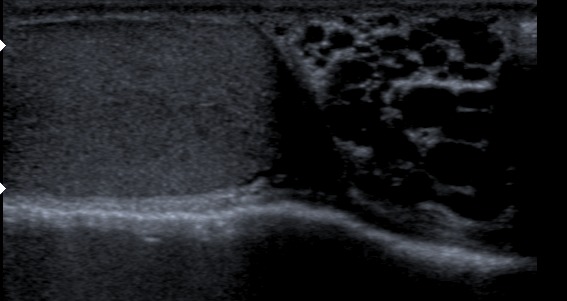

Hydrocele is a fluid collection within the tunica vaginalis.

The inside surface of the scrotum and the testicle are both protected by the membrane known as tunica vaginalis.

Hydroceles are associated with blocked lymphatic drainage or inadequate closure of the processus vaginalis causing communication with the peritoneal cavity.

Hydrocele presents as a transilluminable scrotal enlargement.